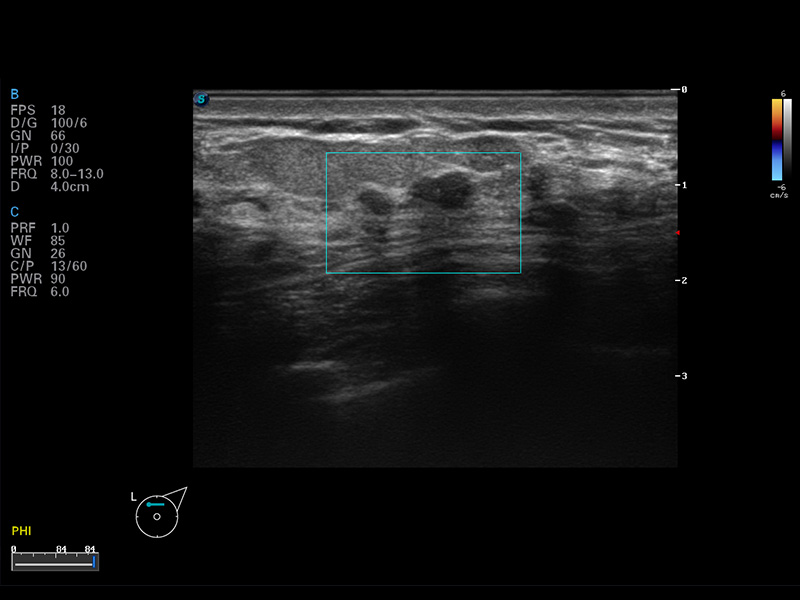

S8 EXP便携式彩色多普勒超声诊断仪是亚星官网研发的高端全身应用型便携彩超。高通道的VIS平台融合可视化(Visual)、智能化(Intelligent)和人性化(Smart)的特点,配以亚星官网自主研发生产的探头大家族,使您能够快速、准确的获得病人信息,提高工作效率的同时减轻疲劳。

μ-Scan微米成像